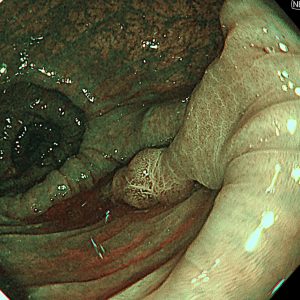

便潜血陽性を認め、人生初めての大腸カメラ検査目的で来院された方です。横行結腸に15mm大の細長いⅠp病変を認めました。拡大NBI観察では一部JNET2A、内視鏡的一括切除を行いました。回収した病変の病理結果は治癒切除でした。上記病変を含めて合計4病変、大腸内視鏡的治療をすることができました。

70歳代 男性 便潜血陽性 #.横行結腸腺腫 15mmⅠp #.多発性大腸腺腫

左:遠景NBI観察、 中:クリッピング術後、 右:病変回収時